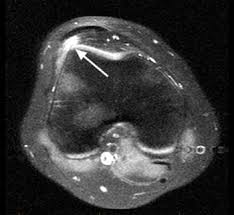

Patients usually present with insidious onset anterior knee pain aggravated by physical activity. MRI shows femoropatellar incongruence with lateral positioning of the patella suggesting lateralizationThis is refered to as excessive lateral pressure syndrome better demonstrated in various femoropatellar articulation X-rays. This may put strain on the medial side and tenderness in the region of the medial patellofemoral ligament MPFL.

Excessive Lateral Pressure Syndrome Mri Sumer S Radiology Blog